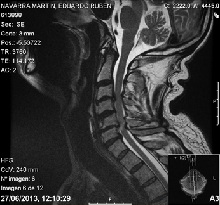

La radiografía ofrece información técnica relevante para la planificación quirúrgica y la resonancia magnética nos indica el grado de compromiso y los niveles afectados. En algunos casos, se solicitan pruebas neurofisiológicas para valorar la cronología del cuadro o ayudar a establecer el diagnóstico diferencial.

En general, se recomienda la cirugía cuando los síntomas son

progresivos o existe un grado de compresión medular evidente con cambios de señal intramedular en la resonancia magnética.